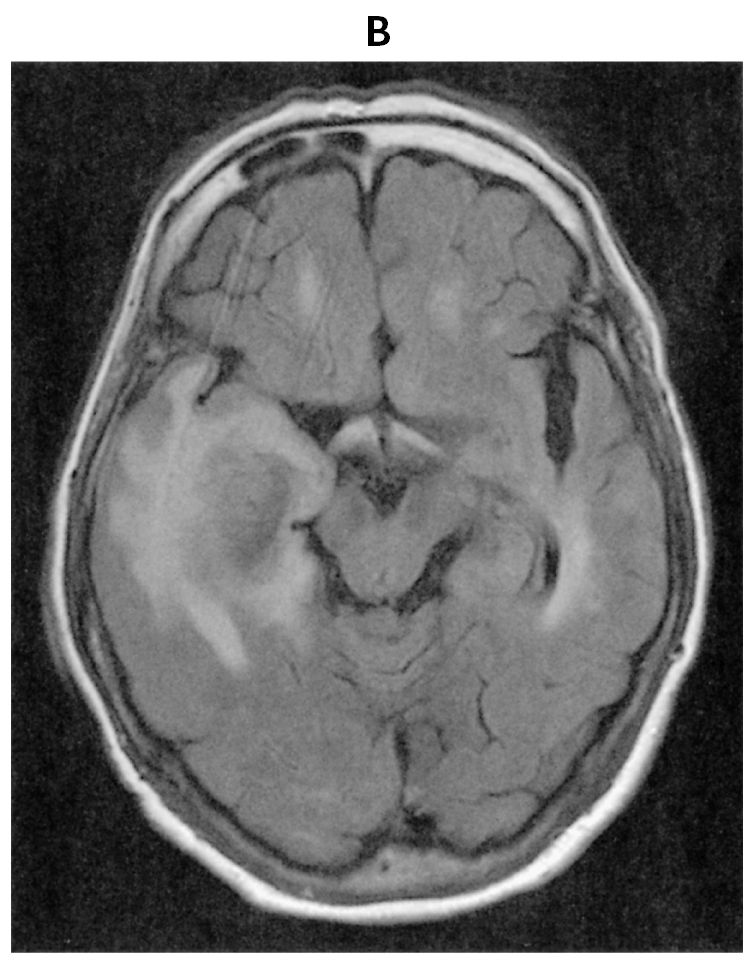

69歳の女性。悪心を主訴に来院した。悪心は3日前から時々自覚していた。既往歴に高血圧症と糖尿病があり,いずれも内服治療中である。慢性腎不全のため5年前に生体腎移植を受け,免疫抑制薬を投与されている。喫煙歴はない。意識レベルはJCSⅠ-1。身長150cm,体重41kg。神経診察で異常を認めない。血液所見:赤血球400万,Hb 12.3g/dL,Ht 41%,白血球6,500,血小板18万。血液生化学所見:総蛋白6.9g/dL,アルブミン4.4g/dL,総ビリルビン0.8mg/dL,AST 22U/L,ALT 10U/L,LD 237U/L(基準124~222),尿素窒素19mg/dL,クレアチニン0.9mg/dL,血糖118mg/dL,HbA1c 6.2%(基準4.9~6.0),Na 140mEq/L,K 4.7mEq/L,Cl 107mEq/L,CEA 2.9ng/mL(基準5以下),CA19-9 2U/mL未満(基準37以下),ProGRP 80pg/mL(基準81以下)。免疫血清学所見:可溶性IL-2受容体685U/mL(基準157~474),CRP 0.1mg/dL。頭部造影MRIのT1強調像(A)と頭部単純MRIのFLAIR像(B)とを下に示す。胸腹部造影CTで異常を認めない。画像所見をもとに病変の生検術を施行した。生検H-E染色標本(C)を下に示す。生検組織内にて増殖を認める細胞は,抗CD20抗体を用いた免疫染色にてB細胞の表面抗原が陽性であった。